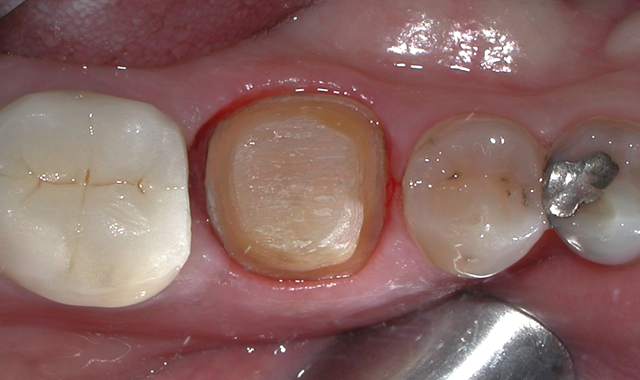

The patient was referred for root canal therapy and after three weeks returned for a restoration (Fig. 2). The tooth was cleaned of temporary restorative material and was prepared for a post and core. A Dentatus Classic Surtex® (Dentatus) metal post was cemented with self-adhesive resin cement (TotalCem, Itena) and an adhesive layer of CLEARFIL SE Bond (Kuraray Dental) was placed as per manufacturer’s instructions, followed by light curing for 10 seconds.

Fig. 2 Fig. 3

The chamber was then filled using CompCore™ AF (Premier Dental). CompCore AF is a dual-cured, fluoride-releasing, radiopaque composite core buildup indicated for vital and nonvital teeth (Figs. 3-4).